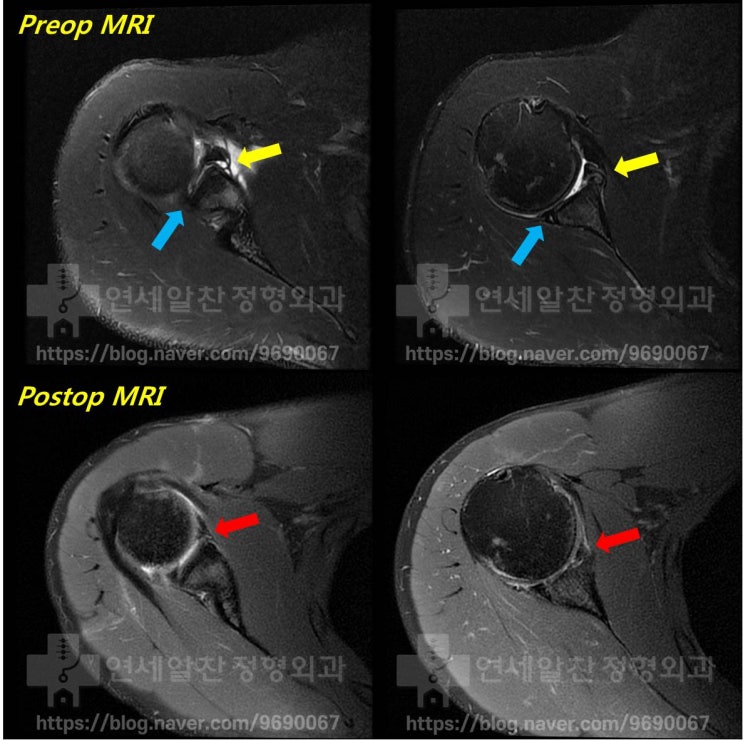

반카르트 봉합술 후 결과 - MRI 상 해부학적 복원

이전에 반카르트 봉합술을 해부학적으로 복원한 환자의 결과에 대해 알아보자 환자는 수술 후 6주차에 수술...